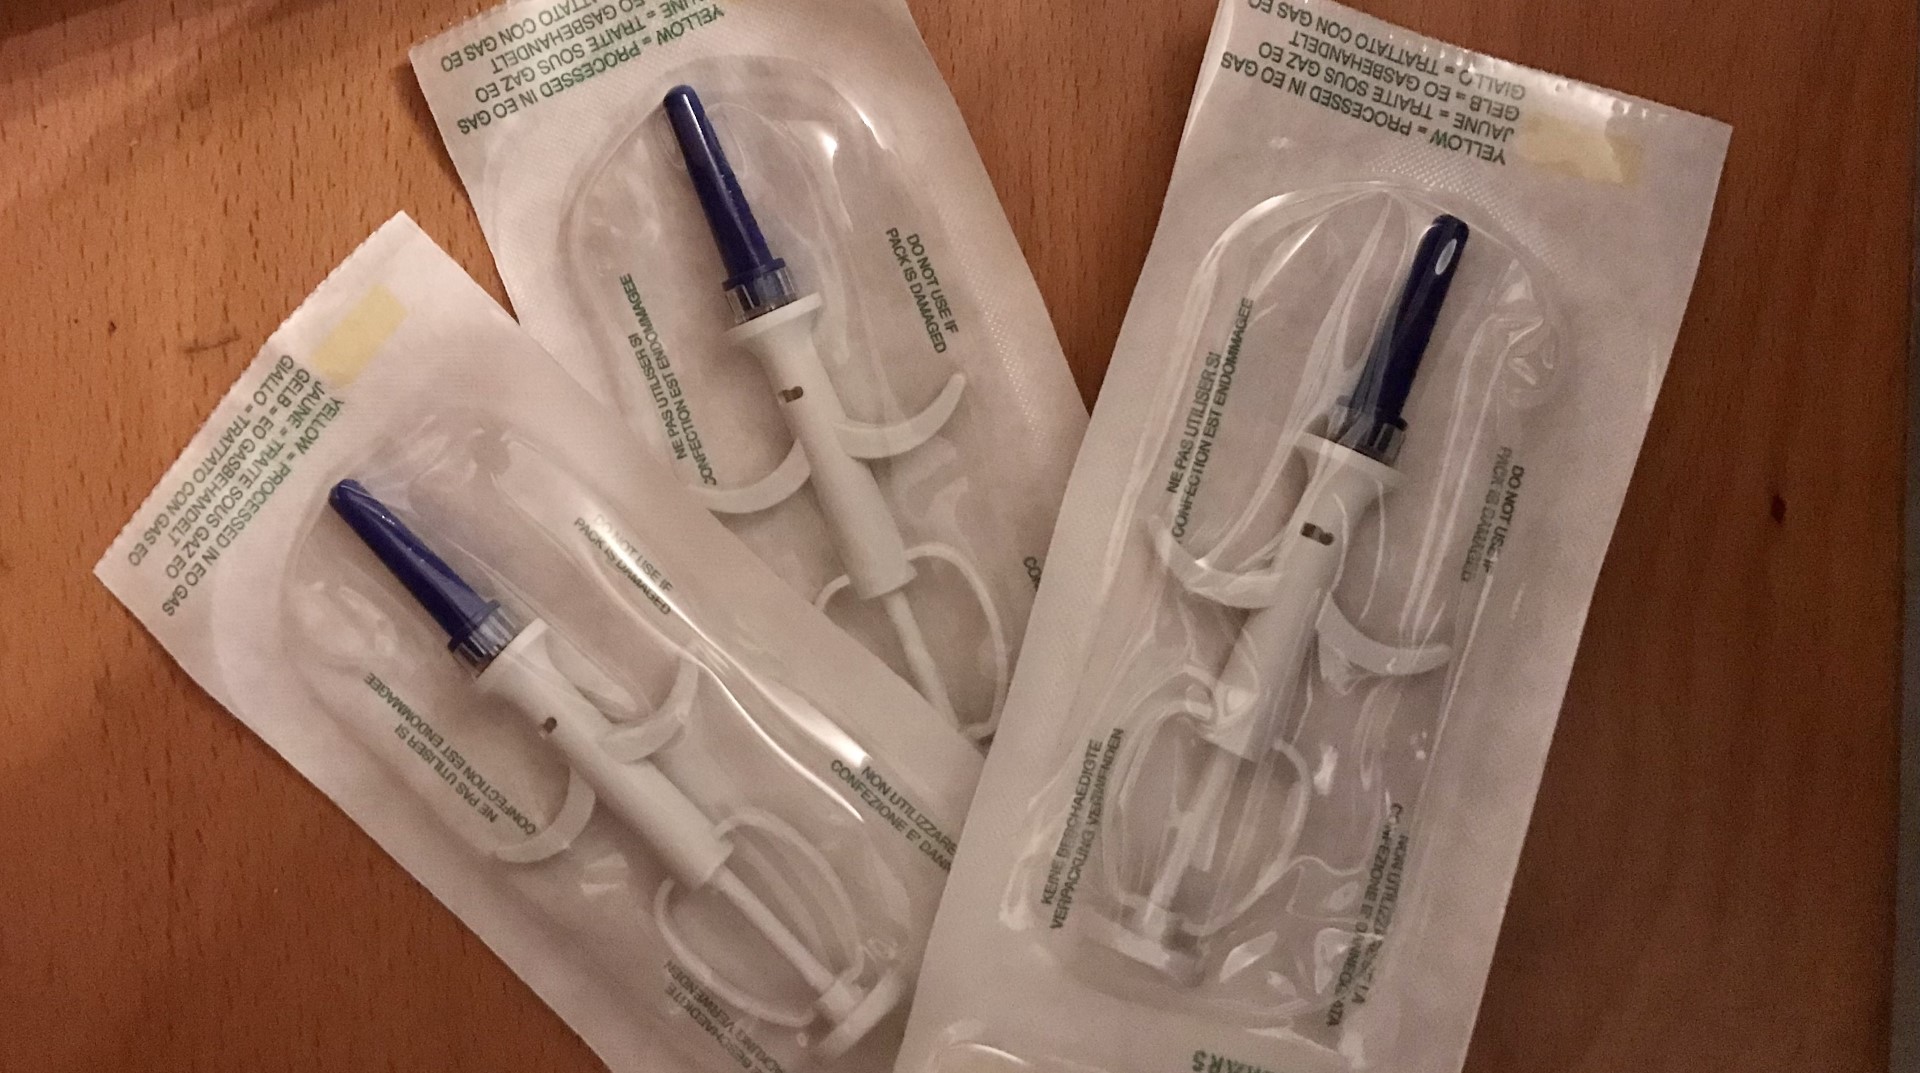

Nieuw leven op stal is altijd een spannende gebeurtenis, toch mogen er enkele belangrijke dingen niet uit het oog verloren worden. Daarom is het aan te raden om na de bevalling merrie en veulen eens te laten controleren door een dierenarts. Hij kan dan ook direct het veulenspuitje toedienen en als nodig een snaptest (controle van de opgenomen antistoffen in het bloed van het veulen) uitvoeren.